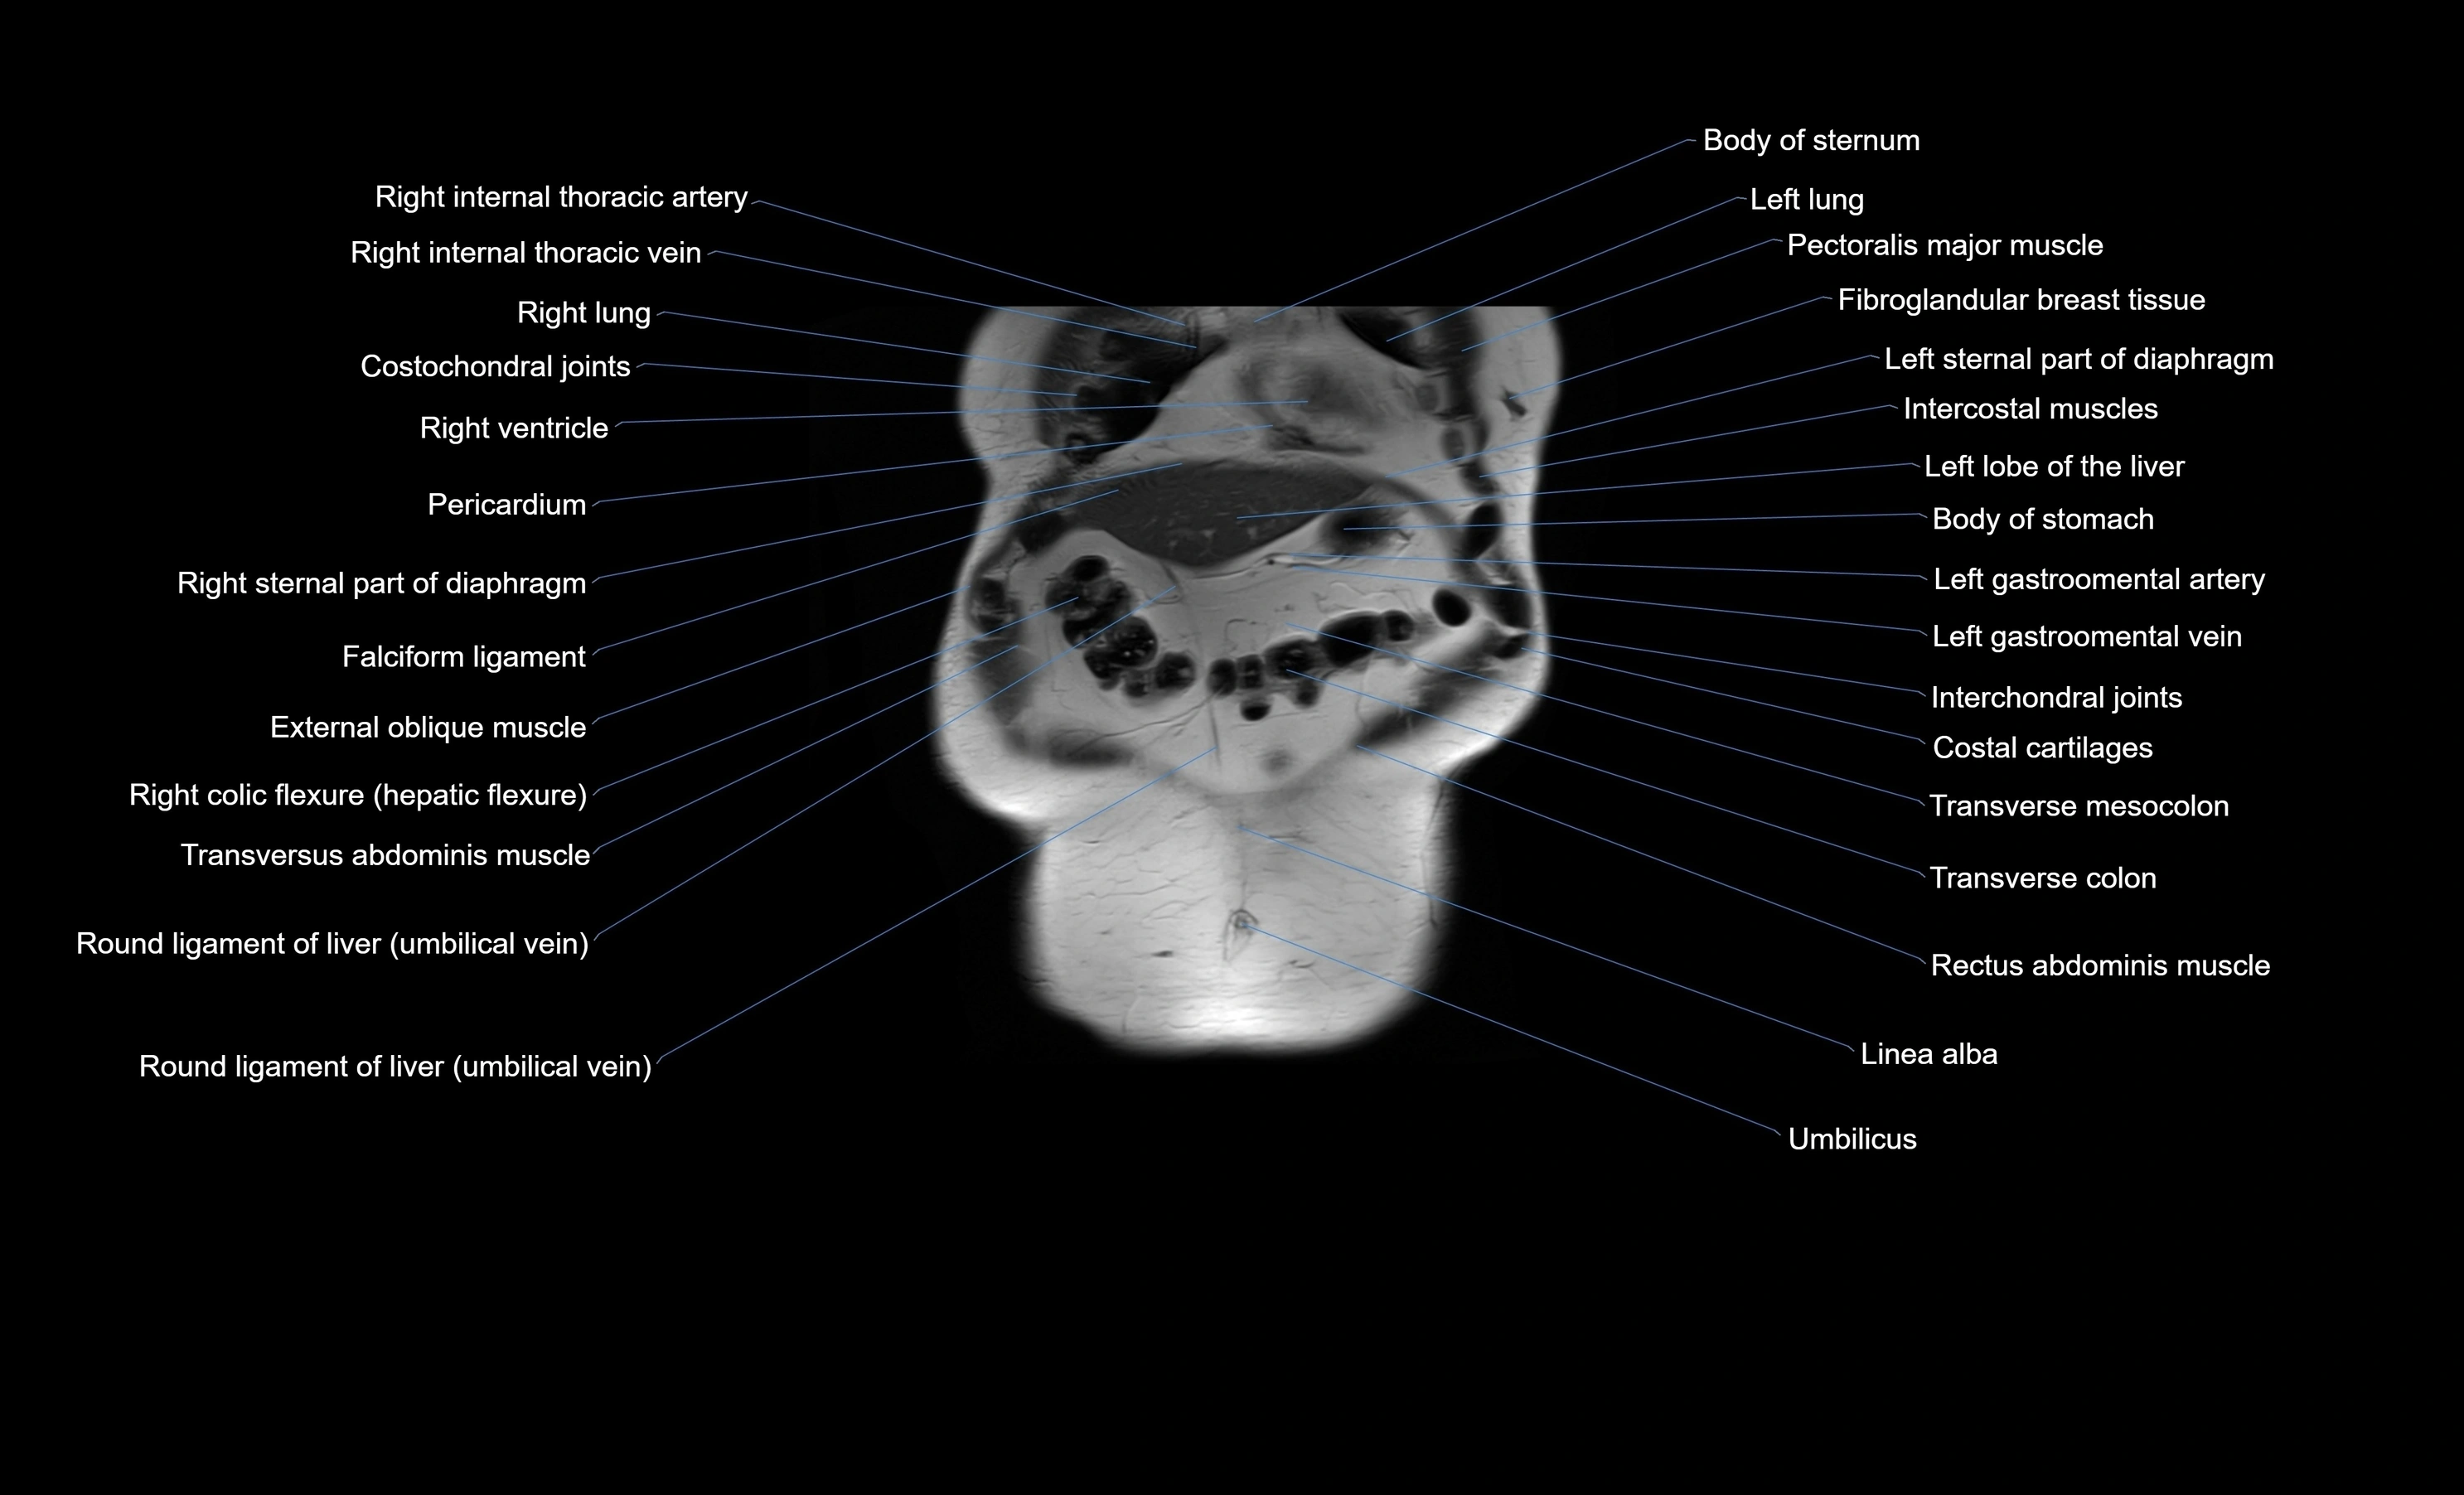

MRI images